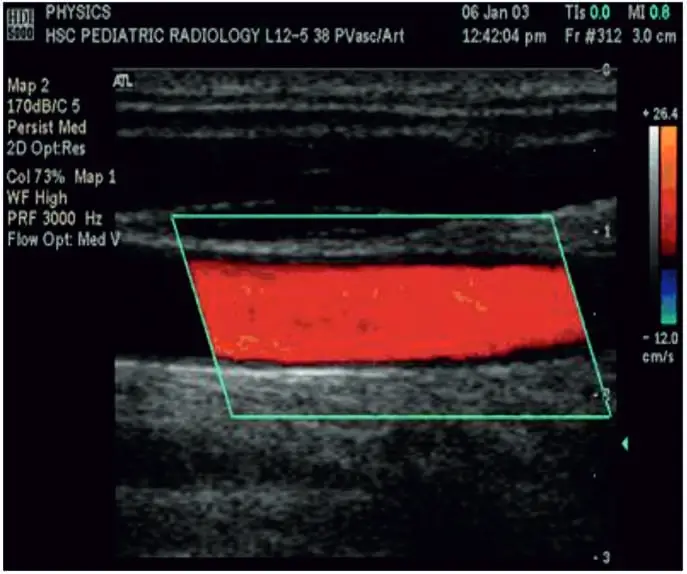

Doppler Sonography

Sonography can be enhanced with Doppler measurements, which employ the Doppler effect to assess whether structures (usually blood) are moving towards or away from the probe, and its relative velocity. By calculating the frequency shift of a particular sample volume, for example a jet of blood flow over a heart valve, its speed and direction can be determined and visualised. This is particularly useful in cardiovascular studies (sonography of the vasculature system and heart) and essential in many areas such as determining reverse blood flow in the liver vasculature in portal hypertension. The Doppler information is displayed graphically using spectral Doppler, or as an image using color Doppler (directional Doppler) or power Doppler (non directional Doppler). This Doppler shift falls in the audible range and is often presented audibly using stereo speakers: this produces a very distinctive, although synthetic, pulsing sound.

With the help of Color Doppler U/S blood flow in both can be diagnosed.